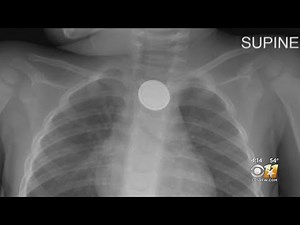

Look Out For Child Choking Hazards

6.2K views

Dec 24, 2020

YouTube

CBS TEXAS